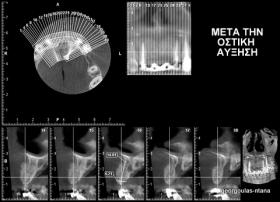

Στην ασθενή αυτή είχαν πραγματοποιηθεί 2 ενδοδοντικές θεραπείες (απονευρώσεις) που ακολουθήθηκαν από 2 ακρορριζεκτομές χωρίς επιτυχία. Η ασθενής ήταν δυσαρεστημένη με την όψη κ το χρώμα των δύο δοντιών και φυσικά με το πρόβλημα υγείας που δημιουργήθηκε. Πραγματοποιήθηκε εξαγωγή των δύο δοντιών, οστική αύξηση και τοποθέτηση 2 εμφυτευμάτων στις θέσεις των δύο κεντρικών τομέων. Τα δύο εμφυτεύματα αποκαταστάθηκαν με 2 υβριδικά κολοβώματα από διπυριτικό λίθιο και ολοκεραμικές στεφάνες ενώ στους 2 πλάγιους τομείς τοποθετήθηκαν επίσης ολοκεραμικές στεφάνες.